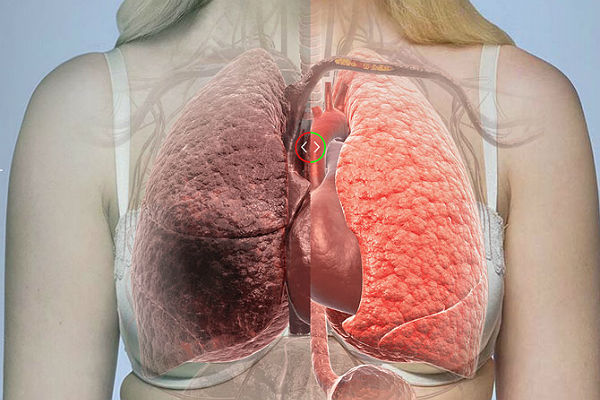

442.4KZdravljeŠokantni snimci otkrivaju ogromnu razliku koju prave vakcine protiv korone

Pluća pacijenata sa kovidom-19 nisu ista - jedan je vakcinisan, drugi nije